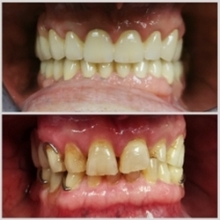

Uzrok promjene boje zubi možemo naći u genetskim i degenerativnim promjenama, antibioticima, starenju kao i u učestaloj konzumaciji obojene hrane i pića, te dodataka prehrani. Do neželjene promjene boje zuba, može doći i nakon endodontskih liječenja.

Više

Za bijelu boju zuba odgovorna je caklina, a trošenjem postaje sve tanja zbog čega tamnija boja dentina dolazi do izražaja, pa zubi izgledaju žući. Za promjenu boje zuba potrebno je promijeniti kemijsku strukturu pigmenta koji se nalaze u samom zubnom tkivu. To se postiže pomoću aktivnih molekula kisika koje ulaze u strukturu zuba uz pomoć hidrogen peroksida, te se vežu na molekule pigmenta, a sam proces je poznat pod nazivom oksigenacija.

U našoj ordinaciji provodimo tri načina izbjeljivanja zubi. Philips Zoom lampom u ordinaciji, udlagama kod kuće, te pojedinačno izbjeljivanje zuba koji je potamnio tzv. interno izbjeljivanje.

Izbjeljivanje u ordinaciji

Zoom WhiteSpeed je inovativan i učinkovit profesionalni sustav izbjeljivanja zubi nizozemskog proizvođača Philips koji koristi najnapredniju tehnologiju LED svjetla. Zoom lampa emitira optimalnu razinu svjetlosti sa znatno većom razinom intenziteta nego ostale LED lampe na tržištu. Svjetlo aktivira foto katalizator unutar Zoom Chairside Gela koji ubrzava i poboljšava rezultate izbjeljivanje te omogućuje odlične rezultate. Intenzitet se može prilagoditi svakoj osobi te tako omogućavamo ugodniji tretman i veće zadovoljstvo rezultatima.

Prije tretmana potrebno je napomenuti imate li izrazito osjetljive zube, kako bi znali prilagoditi tretman i ocijeniti jeste li pogodna osoba za sam tretman. Ako imate krunice ili ljuskice na zubima, njihova boja se izbjeljivanjem neće promijeniti što je kontraindikacija za izbjeljivanje kao i ako imate vidljive kompozitne ispune na prednjim zubima. Prije tretmana potrebno je očistiti kamenac sa površine zubi.

Aktivan sastojak Zoom gela za izbjeljivanje je vodikov peroksid koji ima prirodna svojstva izbjeljivanja, a pod utjecajem svjetla se intenzivira. Zoom lampa svojom specifičnom svjetlošću aktivira vodikov peroksid te mu pomaže ispuniti površinu zuba, nakon čega čisti kisik ulazi u caklinu i dentin te izbjeljuje obojeno područje ostavljajući strukturu zubi nepromijenjenom.

Tretman poslije pripreme zubi traje maksimalno 1 sat (4x15 min). Lampa može izbijeljeti zube do čak 4 nijansi, a učinci izbjeljivanja zubi mogu trajati i do tri godine. Rezultat tretmana izbjeljivanja je individualan, te ovisi o početnoj nijansi zuba, kao i o strukturi zubne cakline. Zoom svjetlo dovodi do minimalnog zagrijavanja koje je najčešće uzrok nelagode. U nekim slučajevima zubi postanu privremeno osjetljivi na hladnoću tijekom i nakon tretmana.

Ovi simptomi obično su privremeni i trebali bi nestati u roku od nekoliko dana nakon završetka tretmana. Nakon tretmana na zube se može nanijeti i ACP gel koji u kratkom roku eliminira bilo kakav osjećaj nelagode. Unutar 48 sati moguća je prolazna preosjetljivost na hladno.